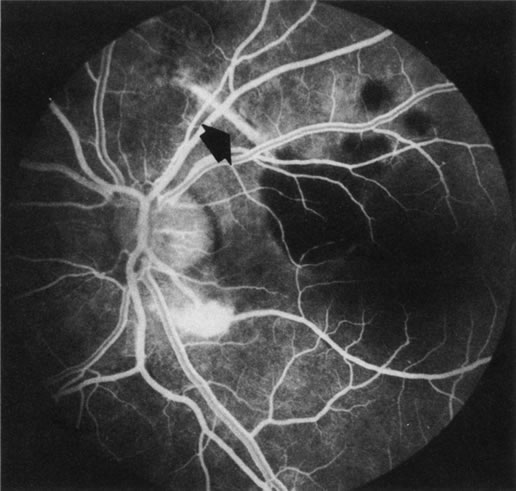

FA is generally not necessary to make the diagnosis of cystoid macular edema (CME). A history of recent cataract surgery, diabetes, uveitis, or other predisposing conditions is usually obtained. Clinically, the patient presents with retinal thickening, often with clinically evident cystic changes. FA reveals a characteristic petaloid collection of fluorescein that confirms the diagnosis, which has been shown histologically to reflect accumulation of fluid in the extravascular component of the outer plexiform layer.239 When FA demonstrates leakage from the optic nerve, this suggests an inflammatory etiology for the CME (Fig. 36). Although this sign is reliably present in CME associated with cataract surgery, penetrating keratoplasty, or posterior uveitis, it is not characteristically present in diabetics or in idiopathic CME. FA can also demonstrate dilated macular capillaries as a cause of CME in diabetes (Fig. 37). Different conditions that may cause CME include Irvine-Gass syndrome, previous penetrating keratoplasty, any inflammatory condition that involves the posterior segment, peripheral rhegmatogenous retinal detachment, peripheral cryotherapy, malignant melanoma, topical epinephrine, tapetoretinal degenerations, juxtafoveal telangiectasia, occult central retinal vein occlusion, nicotinic acid maculopathy, and idiopathic CME.

Fig. 36. Cystoid macular edema (CME). This patient had bilateral vitritis and CME. A. Early-phase photograph of the right eye reveals telangiectasia of the perifoveal retinal capillaries with some early leakage visible temporally. B. Mid-phase photograph of the left eye reveals more intense fluorescence leakage. C. Late-phase photograph of the left eye demonstrates cystic accumulation of fluorescein in a classic “petaloid” configuration. The late-phase staining of the optic nerve head in this fluorescein angiogram suggests an inflammatory cause of the CME.